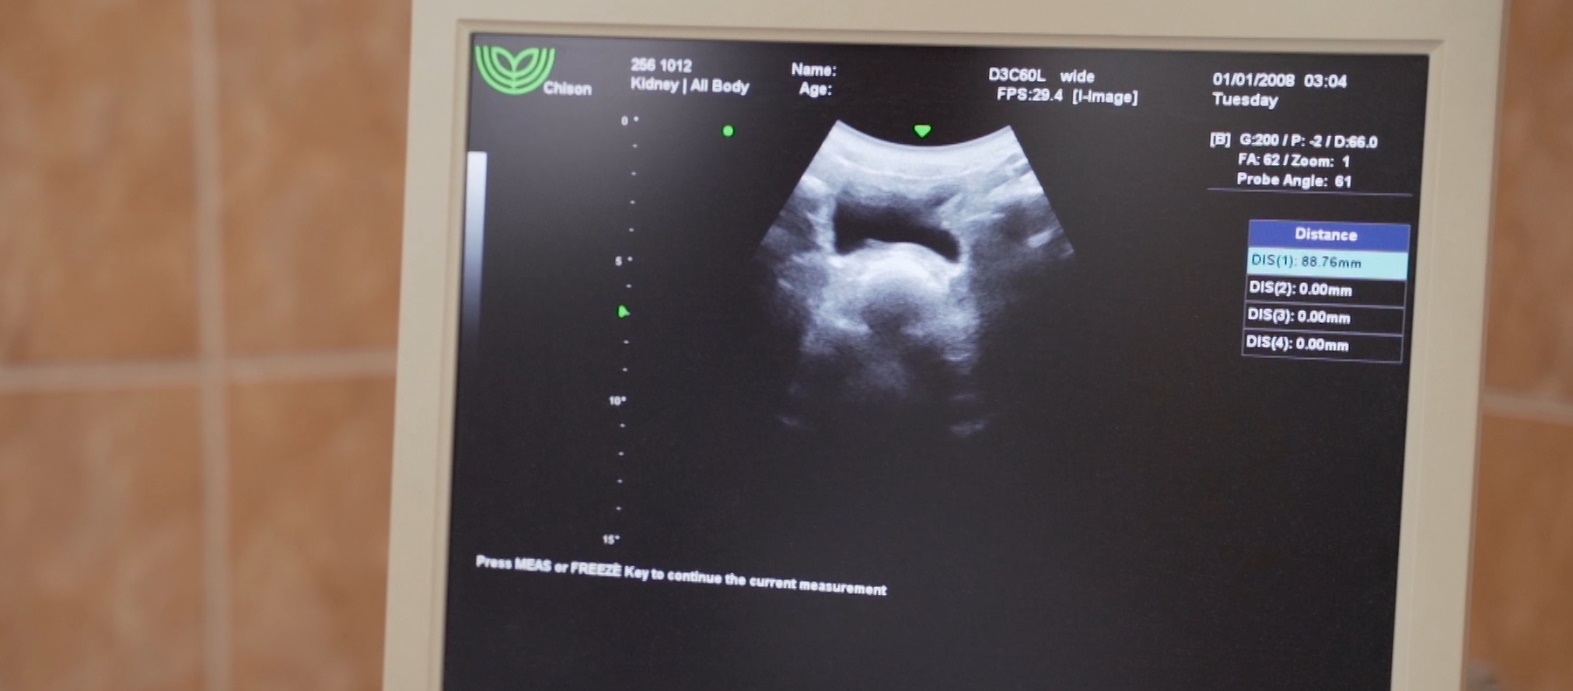

A nefrológia (vesegyógyászat) a vese működési zavaraival foglalkozik.

A vesebetegségek gyakran alattomosan, kifejezett tünetek nélkül jelentkeznek, sokszor csak véletlenül kerülnek felfedezésre az elvégzett labor- és ultrahang vizsgálatok során.